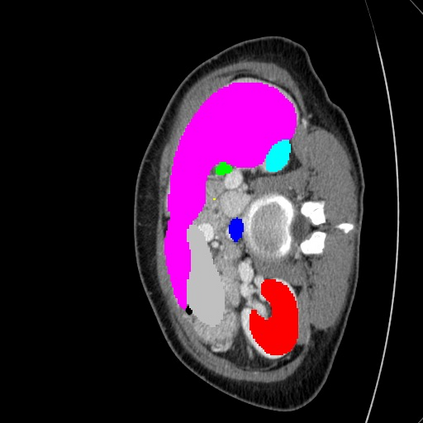

Transformers have made remarkable progress towards modeling long-range dependencies within the medical image analysis domain. However, current transformer-based models suffer from several disadvantages: (1) existing methods fail to capture the important features of the images due to the naive tokenization scheme; (2) the models suffer from information loss because they only consider single-scale feature representations; and (3) the segmentation label maps generated by the models are not accurate enough without considering rich semantic contexts and anatomical textures. In this work, we present CASTformer, a novel type of generative adversarial transformers, for 2D medical image segmentation. First, we take advantage of the pyramid structure to construct multi-scale representations and handle multi-scale variations. We then design a novel class-aware transformer module to better learn the discriminative regions of objects with semantic structures. Lastly, we utilize an adversarial training strategy that boosts segmentation accuracy and correspondingly allows a transformer-based discriminator to capture high-level semantically correlated contents and low-level anatomical features. Our experiments demonstrate that CASTformer dramatically outperforms previous state-of-the-art transformer-based approaches on three benchmarks, obtaining 2.54%-5.88% absolute improvements in Dice over previous models. Further qualitative experiments provide a more detailed picture of the model's inner workings, shed light on the challenges in improved transparency, and demonstrate that transfer learning can greatly improve performance and reduce the size of medical image datasets in training, making CASTformer a strong starting point for downstream medical image analysis tasks.